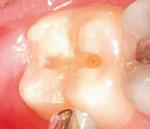

Dr. Bill Waggoner discusses the benefits of using liners along with a case presentation from Dr. Paul Bahn

Cavity liners and indirect pulp capping (IDPC) materials have been used in dentistry for decades. The recent introduction of NuSmile’s NeoLINER™ LC now provides one of the most therapeutic, easy-to-use liners on the market! It is a light-cured MTA-modified bioactive material that is recommended for use as either a cavity liner or as an indirect pulp-capping material. For decades, calcium hydroxide was the most popular lining or indirect pulp-capping material, primarily because of its ability to stimulate reparative dentin. However, its solubility after placement was found to be a problem. Zinc oxide and eugenol, glass ionomers, and resin-modified glass ionomers have also been used as liners, bases, and IDPC materials, but each has shortcomings.

Liners are materials that are placed in thin layers over exposed dentin in the deepest portion of cavity preparations. They function to seal dentin tubules, prevent microleakage, provide some thermal insulation, and depending on the material used, stimulate the formation of reparative or tertiary dentin. Historically, indirect pulp-capping materials have been used when a thin layer of carious dentin remains after deep excavation with no exposure of the pulp and no clinical signs of irreversible pulpitis. In recent years, indirect pulp capping in pediatric dentistry has been utilized when larger amounts of carious tissue remain, but the caries can be sufficiently sealed from the oral environment with a full coverage restoration like a stainless steel or zirconia crown. The main goal of both liners and IDPC materials is to minimize inflammation, promote healing, and maintain vitality of the dental pulp. Indirect pulp capping materials may also demonstrate some bactericidal properties to kill any remaining bacteria that may remain.

The MTA in NuSmile’s NeoLINER LC provides a continuous high calcium release. This, in combination with a high pH, promotes hydroxyapatite formation and protects against hypersensitivity. The high pH also has bactericidal effects to reduce remaining bacteria. NeoLINER LC is packaged in a syringe with 27-gauge disposable tips that allow for precise and easy placement. Its viscosity ensures it will stay in the area where it is placed until it is cured with a curing light. NeoLINER LC is

moisture tolerant, has low water solubility, and is compatible with all etching, bonding, and resin restorative materials. It’s also radiopaque for easy postoperative assessment.

While it is an excellent liner and IDPC material, NeoLINER LC is not recommended for direct pulp capping because of its resin component which can act as an irritant. Any materials containing a resin can damage or kill pulpal tissue if placed in direct contact. If a pulpal exposure is realized, a resin-free MTA material such as NuSmile’s NeoMTA® 2 or NeoPUTTY® is recommended as a direct pulp-capping agent due to its exceptional biocompatibility. These MTA materials, which have a delayed set, may be covered with NeoLINER LC for placement of an immediate final restoration.

Figure 1: Preoperative periapical radiograph of tooth No. 30 with a large radiolucent lesion approximating the distal pulpal horn and a smaller radiolucent lesion closer to the mesial marginal ridge Figure 3: Conservative removal of all carious dentin on all axial walls and pulpal floor. No clinical pulpal exposure noted, but likely very close to distal buccal pulp horn Figure 2: Large active carious lesion involving the entire distal buccal cusp and surrounding aspect of tooth No. 30. Smaller Class VI lesion located on the mesial lingual cusp on No. 30 Figure 4: Placement and curing of two separate thin layers of NeoLINER over the dentin. Image depicts the NeoLINER following the indirect pulp cap of tooth No. 30